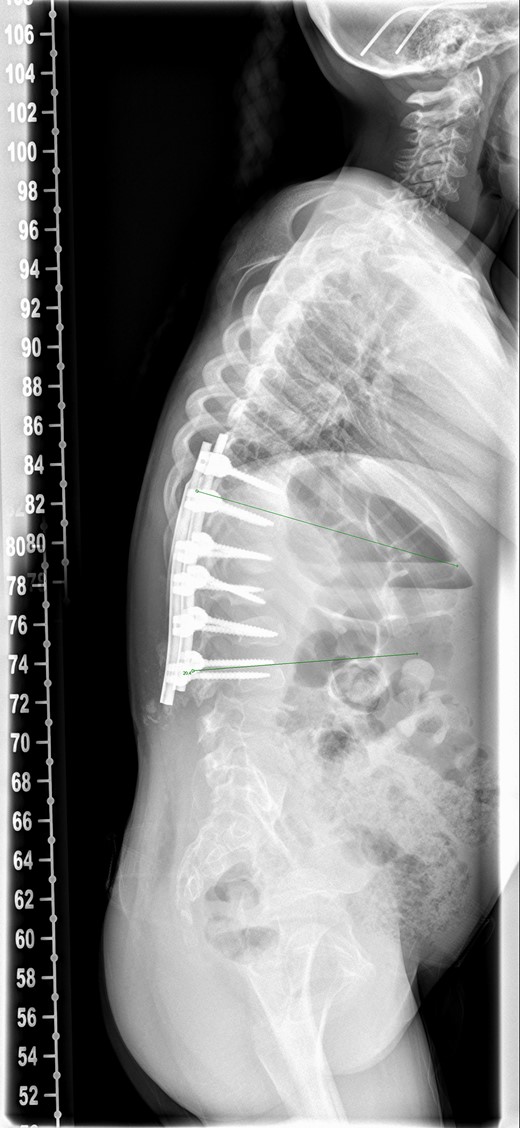

Patient was reviewed 1 month after the surgery and radiographs (Fig. 3a and b) revealed heterotopic ossification in the paraspinal soft tissue. Matured mineralized bone was clearly seen near the distal end of the spinal construct. Wound was healed and there was no further discharge. No further intervention has been planned as patient remains asymptomatic with good radiographic correction of kyphosis.

One month postoperative spine radiograph in (a) lateral view and (b) anteroposterior view showing heterotopic ossification.